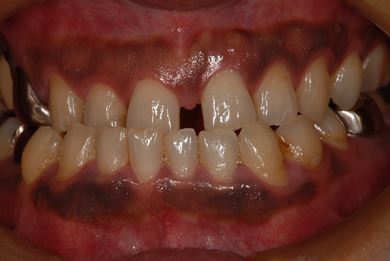

主訴 前歯のすき間を治したい。

治療方針 上顎前歯をオールセラミッククラウンにて審美的回復を行う。

治療内容 CAD/CAMオールセラミッククラウン2本

治療前

• 治療前